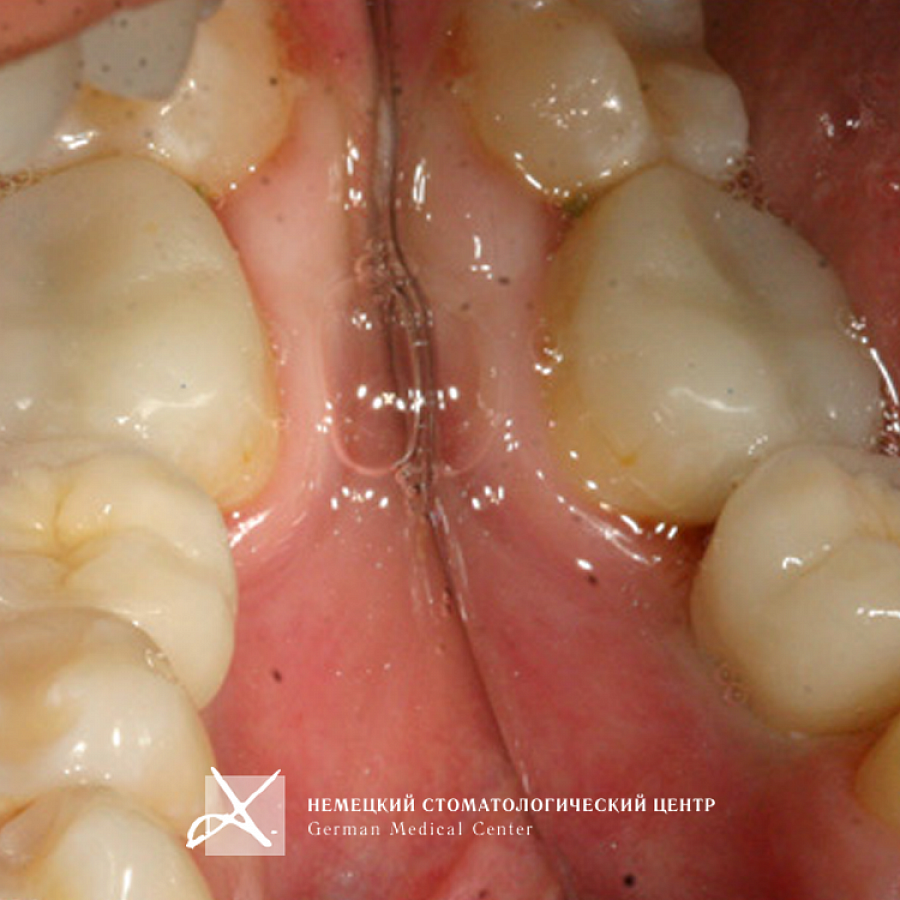

Пациентка обратилась с жалобой на отсутствие зуба 36.

1. Проведена имплантация отсутствующего зуба.

2. Для оптимальной эстетики была изготовлена коронка с каркасом из оксида циркония с использованием индивидуального абатмента, выполненного из аналогичного материала по технологии CAD/CAM. Диоксид циркония (ZrO2) обладает высочайшей степенью биологической совместимости.